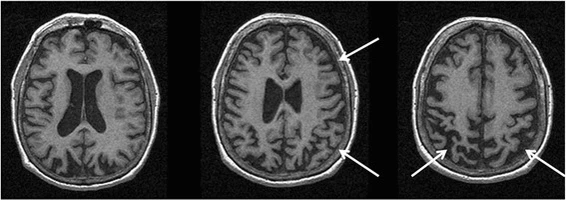

Кортикобазальная дегенерация — это асимметричная атрофия лобно-теменной коры, в базальных ганглиях и в чёрном веществе[1][2]. Выраженность и распределение изменений коррелируют с клиническими синдромами: синдром Ричарсона, фронтотемпоральная дольковая дегенерация или первично прогрессивная афазия. Также определяются тау-позитивные астроцитальные бляшки и волокна в белом и сером веществе, в особенности в верхней теменной и в верхней лобной извилине, в пре- и постцентральной извилине и в стриатуме.